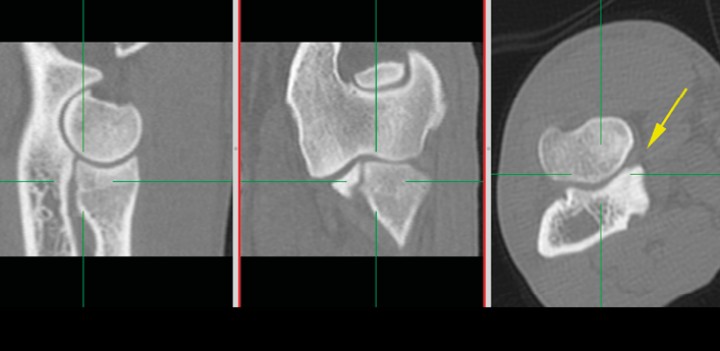

La valoración de la congruencia articular la realizamos con el visor Horos© mediante reconstrucciones ortogonales en 2D, partiendo del plano transversal y realizando reconstrucciones ortogonales con los ejes siempre perpendiculares entre sí (reconstrucción 2D ortogonal) (Fig. 12), y en casos dudosos inclinando los planos de corte y adaptándolos a la morfología de la apófisis coronoides medial (forma conocida como reconstrucción multiplanar en 3D), que nos proporciona una visión más exacta de la congruencia articular (Fig. 13) (Vídeo 5).

<p>Reconstrucción en 2D ortogonal clásica. Con el plano transversal obtenido, el software produce planos sagitales o dorsales. Si se observan las líneas verdes, los planos son siempre perpendiculares entre sí y, a su vez, perpendiculares al plano transversal al que tienen como referencia. No es el más adecuado para valorar la congruencia articular de superficies curvadas. Se señala la ACM (flecha amarilla).</p>

Reconstrucción en 2D ortogonal clásica. Con el plano transversal obtenido, el software produce planos sagitales o dorsales. Si se observan las líneas verdes, los planos son siempre perpendiculares entre sí y, a su vez, perpendiculares al plano transversal al que tienen como referencia. No es el más adecuado para valorar la congruencia articular de superficies curvadas. Se señala la ACM (flecha amarilla).

<p>Reconstrucción 3D MPR multiplanar. Esta forma de reconstrucción permite orientar los ejes según se desee. Cada eje tiene un color y produce la imagen correspondiente en el recuadro del mismo color. El eje marrón es tangencial a la ACM y ofrece la mejor vista para valorar la congruencia articular del codo. Espacio articular humero-radial (flecha roja), espacio articular húmero-cubital (flecha azul), escalón entre la apófisis coronoides lateral y la epífisis proximal del radio (flecha marrón).</p>

Reconstrucción 3D MPR multiplanar. Esta forma de reconstrucción permite orientar los ejes según se desee. Cada eje tiene un color y produce la imagen correspondiente en el recuadro del mismo color. El eje marrón es tangencial a la ACM y ofrece la mejor vista para valorar la congruencia articular del codo. Espacio articular humero-radial (flecha roja), espacio articular húmero-cubital (flecha azul), escalón entre la apófisis coronoides lateral y la epífisis proximal del radio (flecha marrón).